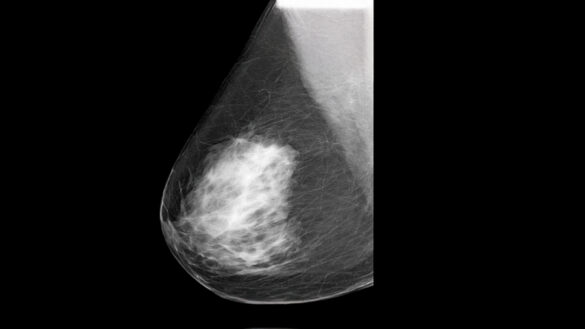

1. Bulto o masa en el seno o la axila 🍊

Puede sentirse duro, irregular o diferente al tejido habitual. No todos duelen.